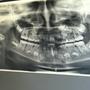

[ teeth_salon (牙齒美容保健) ] 牙齒美容保健